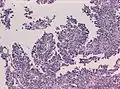

Менинготелиоматозная менингиома состоит из мозаикоподобно расположенных клеток с овальным или округлым ядром, которые содержат умеренное количество хроматина. Строма опухоли представлена немногочисленными сосудами и тонкими тяжами соединительной ткани, которые окаймляют клеточные поля. Характерны концентрические структуры из наслаивающихся одна на другую уплощённых опухолевых клеток. Центр новообразования часто обызвествлён[3].

Фиброзная менингиома состоит из фибробластоподобных клеток, которые располагаются параллельно друг другу и складываются в переплетающиеся между собой пучки, которые содержат соединительнотканные волокна. Ядра вытянутые. Могут встречаться концентрические структуры и псаммомные тельца__[3].

Переходная менингиома включает элементы менинготелиоматозной и фиброзной менингиом[3].

Псаммоматозная менингиома содержит большое количество псаммомных телец[3].

Ангиоматозная менингиома обильно васкуляризирована, содержит большое количество кровеносных сосудов[7].

Микрокистозная менингиома содержит большое количество микрокист, окружённых опухолевыми клетками звёздчатой формы[8].

Секреторная менингиома является редким гистологическим вариантом данного новообразования. Для неё характерна секреция веществ, которые формируют гиалиновые включения[9].

Менингиомы с обилием лимфоцитов по определению содержат большое количество включений лимфоцитарных масс.

Для метапластических менингиом характерна метаплазия (трансформирование) менинготелиальных клеток в клетки другого типа (к примеру адипоциты)[10].